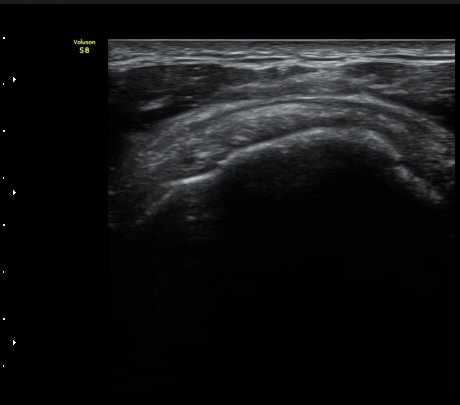

ÀÌµÎ¹Ú±Ù°Ç È¾´Ü¸é°Ë»ç¿¡¼­ ƯÀÌ ¼Ò°ßÀ» º¸ÀÌÁö ¾ÊÀ½(»çÁø 1, 2).

±Ø»ó°Ç Á¾´Ü¸é°Ë»ç¿¡¼­ ´ë°áÀý°ú »ó¿Ï°ñµÎ ÀÌÇàºÎÀ§¿¡ ÇÇÁú°ñ ¿¬¼Ó¼º ¼Ò½ÇÀ» º¸ÀÓ(±×¸² 3, 4, 5)